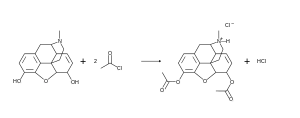

Se obtiene mediante un proceso de acetilación de la morfina[53]

La materia prima para uso industrial o de laboratorio durante la síntesis de la heroína es la morfina. La acetilación con anhídrido acético o cloruro de acetilo se produce durante el calentamiento. No es necesario un exceso de cloruro de acetilo, ya que en este caso, el resultado, cloruro de hidrógeno, se une a la parte básica de nitrógeno núcleo morfinanovogo, y parcialmente retirado de la mezcla de gas que desplaza el equilibrio casi por completo hacia la formación de derivados diacetilados. El crudo de la acetilación se purifica por adición de carbón activo y filtrado para ser posteriormente recristalizado en etanol.

El rendimiento de la reacción es de hasta del 95,5%.[54]

Los reactivos acetilantes están incluidos en la lista de precursores de estupefacientes y el tráfico en muchos países está limitado y controlado en conformidad con la ley y los tratados internacionales.[55]